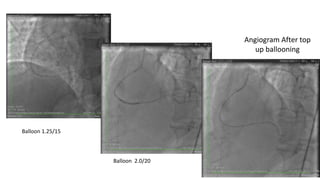

Balloon 1.25/15 for

Channel crossing

Balloon 1.25/15

Balloon 2.0/20

Angiogram After top

up ballooning